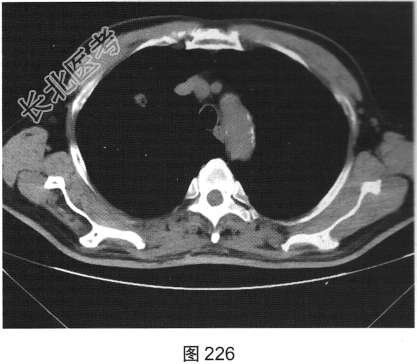

- [材料题] 患者女性,70岁。因“咳嗽、痰中带血3个月余”就诊。听诊无异常发现。胸部正侧位片发现右肺上叶类圆形小结节。

- 简答题2、患者行胸部CT检查,如图225、图226所示。请问该患者CT图像可见什么阳性表现?